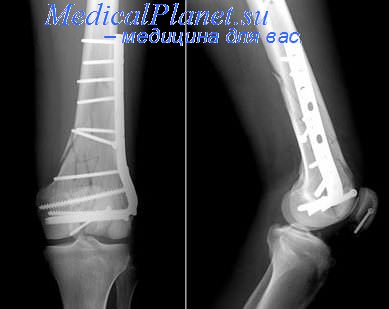

Как и при любой травме коленного сустава для постановки правильного диагноза выполняется рентгенография, на которой-то и можно увидеть перелом. Обычно рентгенографию выполняют в прямой и боковой проекциях, а для диагностики вертикальных переломов выполняют еще и осевую (аксиальную, или Merchant) проекцию.

Прямая (слева) и боковая (справа) проекции, на которых виден горизонтальный перелом надколенника со смещением отломков. Осевая проекция. Вертикальный перелом. Обратите внимание на возникшую в результате смещения ступеньку на скользящей поверхности надколенника.

Определить вид перелома согласно классификации – переломы в области коленного сустава классифицируются как А, В, С. Соответственно это определяет перелом является внутрисуставным или нет.

К сожалению, рентгенография не всегда дает полную картину перелома, особенно перелом внутрисуставной. Для лучшего понимания перелома необходима дополнительная диагностика. Я всегда пользуюсь компьютерной томографией, которая помогает правильно спланировать операцию, подобрать правильные пластины, длину винтов.

Следующая часть не менее важная, это выбор фиксатора для скрепления переломов. Если перелом произошел на фоне остеопороза (обеднение кости кальцием), применяют специальные фиксаторы. Так называемые блокирующие пластины, которые являются «золотым стандартом» в современной травматологии.

Контроль стояния отломков на операционном столе это очередное условие успеха оперативного вмешательства. Благодаря современной мобильной рентгенследящей установки в нашей операционной качества выполнения операций значительно повысились.